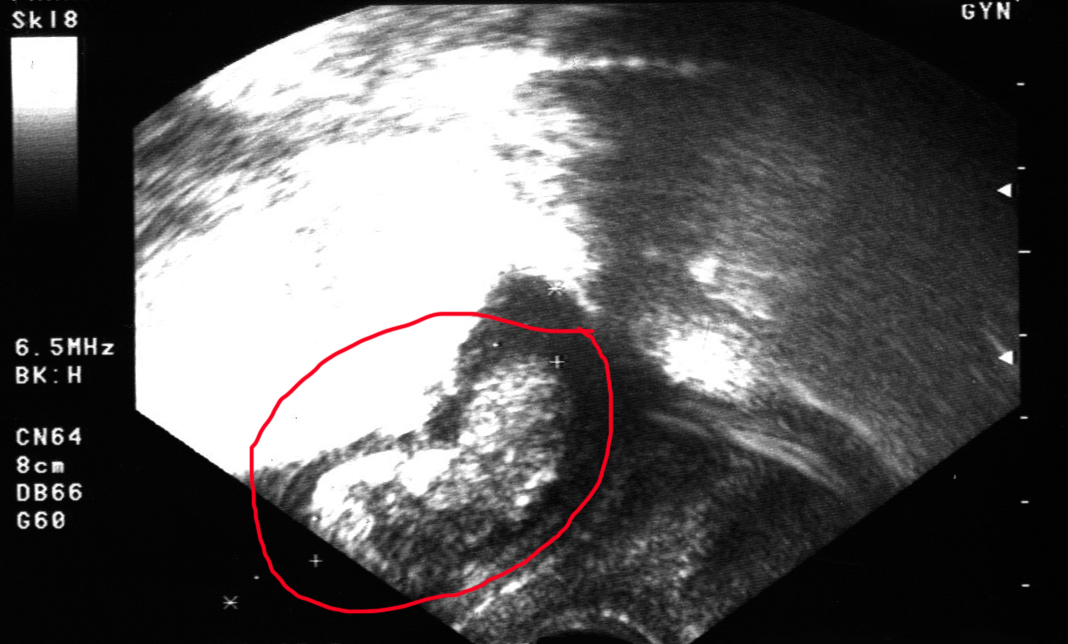

Ich bin jetzt am Ende der 11. Schwangerschaftswoche und habe heute endlich meinen Mutterpass bekommen. Der Termin bei meinem Gyn war unchristlich früh, wir (diesmal war mein Freund mit dabei) mussten schon um 6.30 Uhr aufstehen. Einplanen sollte ich eine gute Stunde, mir wurde jede Menge Blut abgezapft (Blutgruppenbestimmung, HIV-Test, Antikörper-Suchtest, Hb-Wert, und so weiter…), mein Blutdruck wurde gemessen, ich musste auf die Waage und in einen Becher pinkeln, außerdem durfte ich mich noch ausführlich von meinem Doc beraten lassen – es ging um Ernährung (Hauptsache ausgewogen, eh klar), Zahngesundheit (Karies kann eine Fehlgeburt auslösen – das wusste ich nicht) und natürlich darum, dass man als Schwangere auf Genussmittel tunlichst verzichten sollte – also kein Alkohol und keine Zigaretten (das wusste ich natürlich schon, aber er hat mir auch noch einmal genau erklärt, dass man eben nicht genau weiß, zu welchen Zeitpunkten in der Schwangerschaft Gifte den größten Schaden anrichten und dass man deshalb am Besten komplett darauf verzichtet). Am Ende durfte ich dann auf die Liege und es wurde der zweite Ultraschall gemacht – unglaublich, wie sehr sich das Würmchen schon weiter entwickelt hat: Man konnte jetzt schon deutlich die Extremitäten ausmachen und mein Freund hat sogar gesehen, wie es sich einmal um sich selbst gedreht und dabei mit den Ärmchen gerudert hat. Die Ausdrucke sind ja immer recht enttäuschend, weil die Bewegung fehlt, ich lade Euch meinen trotzdem hoch.